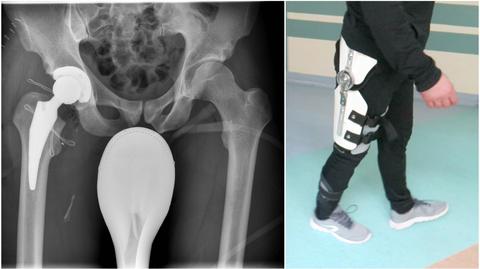

Wyjątkowy pacjent, wyjątkowy lekarz i niezwykła operacja. Ciężko ranny antyterrorysta po strzelaninie przed bankomatem trafił na stół operacyjny wrocławskiego mistrza. Doktor Domanasiewicz wykonał pierwszą w Europie rekonstrukcję nerwu kulszowego, pobierając nerwy od zmarłego dawcy. Policjant wraca do zdrowia i chce wrócić do służby.